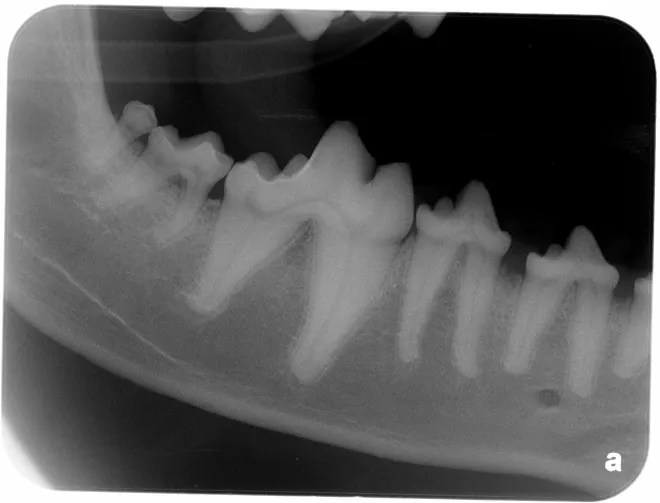

Dog Dental X Rays . Radiographs are absolutely critical in cases of periodontal disease of the mandible of small and toy breed dogs (especially in the area of the canine and first molar teeth). The procedure is safe and painless for your dog, and it provides crucial information about their oral health that cannot be obtained through visual examination alone. This article focuses on interpretation of normal anatomic variations as well as congenital and pathologic abnormal findings on dental radiographs in dogs and cats (box 1). These units are portable or wall mounted. They have flexible arms that allow. Let's dive in to canine dental radiographs. To isolate the first and second maxillary molars, berg places the caudal edge of the digital sensor at the caudal edge of the.